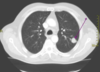

Use these for diagnosis of what?

- Radiographically presents with nodular, irregular, pleural thickening, poss pleural effusion, and pleural plaquing

- CXR

- CT

- Thoracentesis

- Surgical biopsy

- Usually necessary for diagnosis

- Difficult to diagnose

- PET

- Helpful in ?malignancy; staging; poss surgical candidate

Mesothelioma